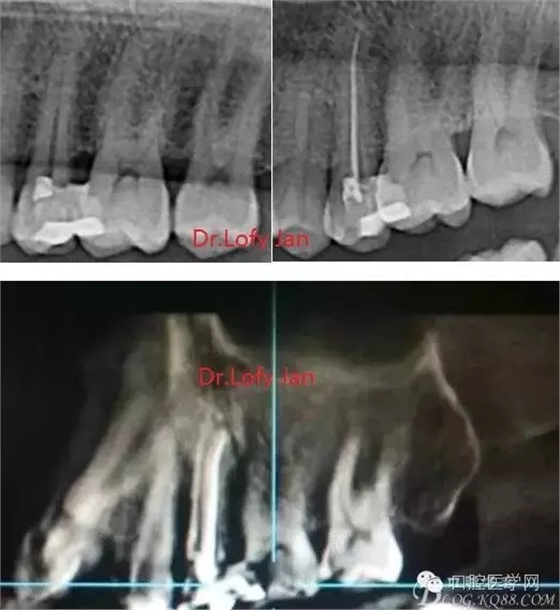

曲面斷層片在未試尖根管治療中的病例整理

前言:自己做的一些曲面斷層片在未試尖根管治療中的病例整理,發(fā)現(xiàn)問題很多包括自身的,技術(shù)的,還有設備的問題,予以總結(jié)整理并期待進一步提高。

《數(shù)字化根尖片、曲面斷層片、CBCT測量牙齒長度準確性的比較研究》文中顯示:平行投照數(shù)字化根尖片影像長度和牙齒實際長度之間無顯著性差異(P0.05);數(shù)字化曲面斷層片影像長度和牙齒實際長度之間有顯著性差異(P0.05),平均失真率為17.05%。CBCT冠狀面測量結(jié)果中除上頜前磨牙區(qū)、下頜前磨牙區(qū)與真實長度差異無統(tǒng)計學意義(P0.05)外,其余6個分區(qū)差異均有統(tǒng)計學意義(P0.05);矢狀面測量結(jié)果中上頜磨牙區(qū)、下頜磨牙區(qū)、下頜前磨牙區(qū)、下頜尖牙區(qū)、下頜前牙區(qū)與真實長度比較差異均有統(tǒng)計學意義(P0.05)。結(jié)論平行投照數(shù)字化根尖片較曲面斷層片和CBCT能更加精確地反映牙齒的真實長度。

病例分析:曲面斷層片在x線輔助診斷與檢查中目前大多數(shù)文獻和著作都建議只能作為初診拍片檢查手段,不能作為終末疾病的確診與手術(shù)療效的評價指標,臨床大部分中小型門診都因為設備不齊全導致信息偏差很大。